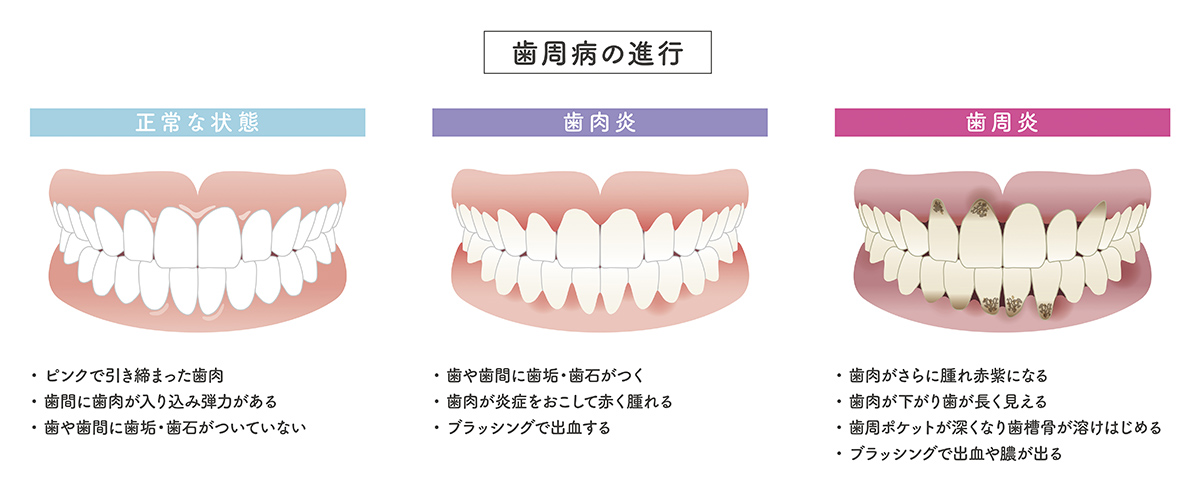

歯周病とは

むし歯以上に歯を失うリスクの高い歯周病。歯垢に含まれた歯周病菌に感染することで、歯周組織が壊されていく病気です。痛みがないまま進行する特長を持つため 「静かなる病」ともいわれています。